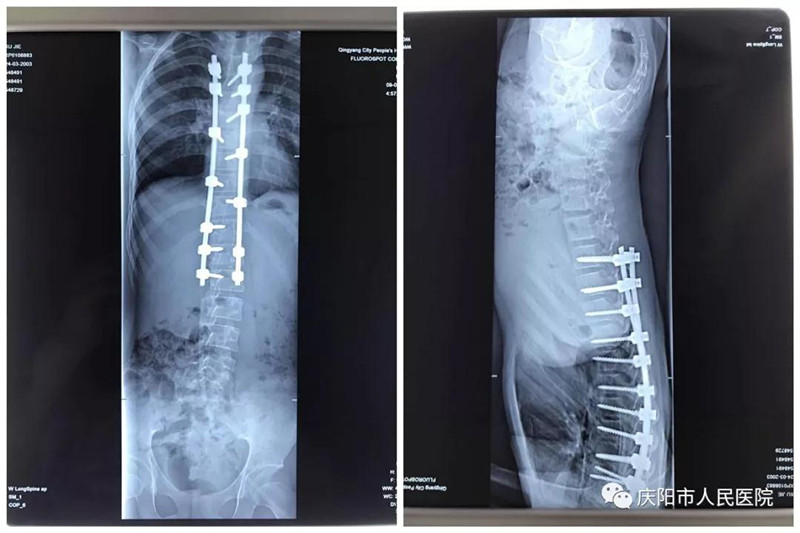

特發(fā)性脊柱側(cè)凸畸形矯形手術(shù)成功實施。脊柱側(cè)凸俗稱脊柱側(cè)彎,是一種脊柱的三維畸形,包括冠狀位、矢狀位和軸位上的序列異常,這是繼脊柱后凸畸形矯形手術(shù)開展以來,我院骨一科在脊柱外科領(lǐng)域的又一項成就,標(biāo)志著我院脊柱外科技術(shù)又向前邁進了一步。